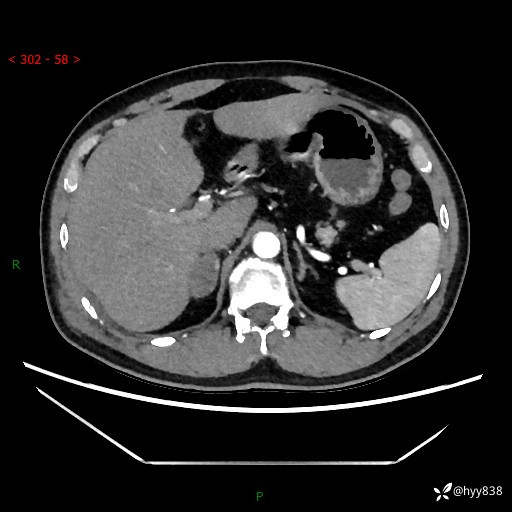

现病史:患者9月4日摔伤在深圳市宝安区中心医院行CT检查提示右侧肾上腺区结节(38*27mm),复查B超提示右侧肾上腺区可见一61*24mm异常低回声团,建议进一步检查。进一步完善增强CT后提示:右侧肾上腺区肿块及周围渗出改变,大致同前,考虑肾上腺腺瘤,不除外瘤内出血可能,否认阵发性头晕、头痛、出汗、乏力等不适,门诊以“ 右侧肾上腺肿瘤”收入住院。 起病来,患者精神、食欲、睡眠可,大便通畅,小便如上述,体力体重无明显改变。

肾上腺CT平扫

增强(动脉期+静脉期)